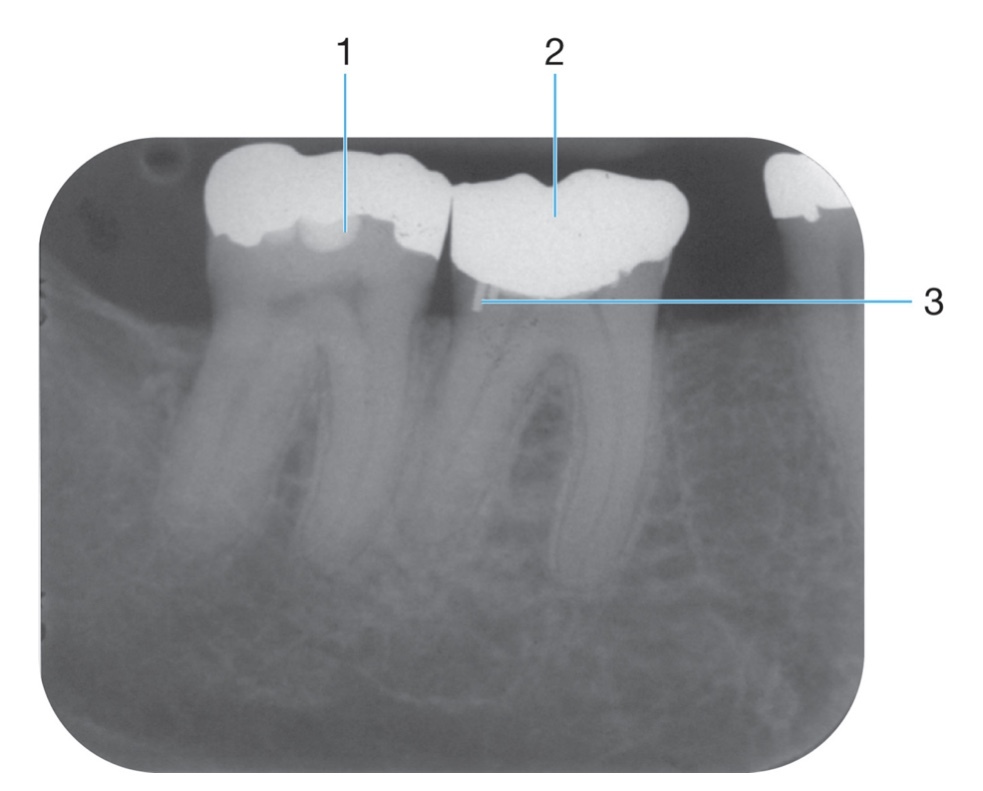

1.

PDL space

Name the classification of dental caries illustrated by 3

C-3 Advanced Caries

Advanced: Lesion that extends to or through the DEJ but does not extend more than half the distance to the pulp

Identify #1.

Border of maxillary sinus

Identify the age of this patient

Age 8